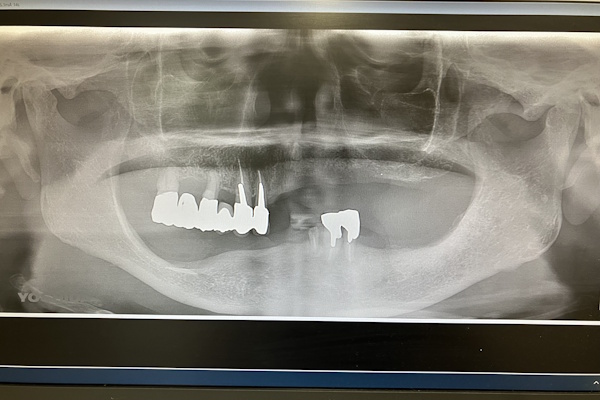

レントゲン画像